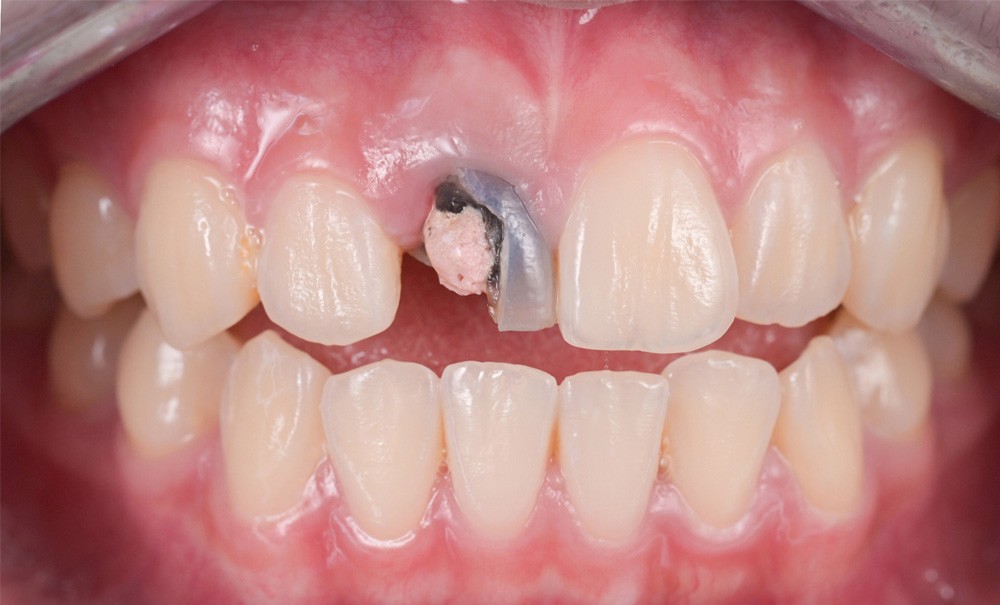

Depuis plus de vingt ans, les bridges collés à une seule ailette – dits cantilevers ou mono-ailettes – n’ont cessé d’évoluer. Solution souvent choisie en deuxième intention quand l’implant n’était pas envisageable ou à titre temporaire, ces bridges sont considérés aujourd’hui comme faisant partie intégrante de l’arsenal thérapeutique permettant le remplacement d’une incisive.

Si, au début, le choix des matériaux et des protocoles étaient assez empiriques, la technique est aujourd’hui bien codifiée, portée par les progrès en sciences des matériaux et en adhésion. Le Professeur Matthias Kern [1], pionnier de la technique des bridges collés cantilevers, a ouvert une voie que la dentisterie contemporaine ne cesse d’affiner. Aujourd’hui, les indications et la mise en œuvre de ces bridges sont validées aussi bien scientifiquement qu’administrativement. Ils figurent même depuis 2018 à la nomenclature de la sécurité sociale sous le code HBLD093.

Comme pour tout traitement prothétique, le clinicien est confronté à des choix qui ne sont pas toujours simples. Dans le cas de l’édentement unitaire antérieur, le choix du bridge collé face à l’implant doit répondre à des critères stricts.